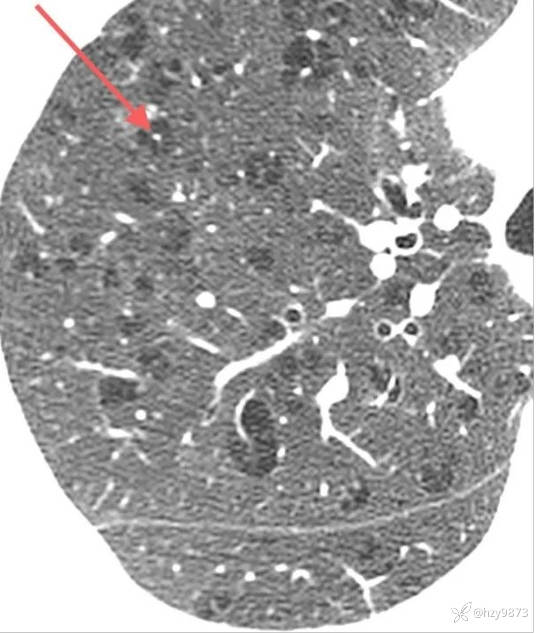

Fleischner 学会将肺气肿分为三类:

1) 小叶中央型肺气肿(centrilobular emphysema)

2) 全小叶型肺气肿(panlobular emphysema)

3) 间隔旁气肿(paraseptal emphysema)